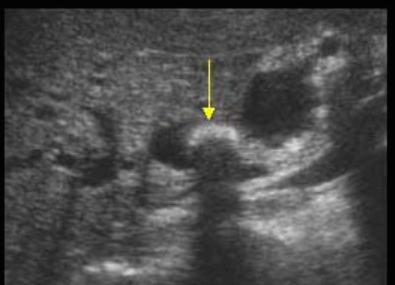

- 담석이 관찰되지 않고 간외, 간내담관의 확장소견을 시사하는 엽총징후(shotgun sign)이나 평행관 징후(parallel channel sign)가 관찰되기도 한다.

- 엽총징후(shotgun sign): 간외 담관이 확장되어 간외 담관과 문맥이 이웃해 관찰된다.

- 평행관 징후(parallel channel sign): 간내 담관이 확장되어 인접하고 있는 문맥과 나란히 2개의 관상구조로 나타난다.